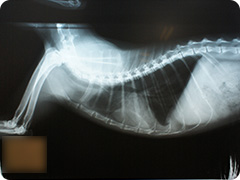

- 骨折

- 高いところから飛び降りたりすることで骨折することがあります。骨折した足はぶらーんとして床に足を付けられない状態になります。

創外固定法による治療

プレートを用いた治療